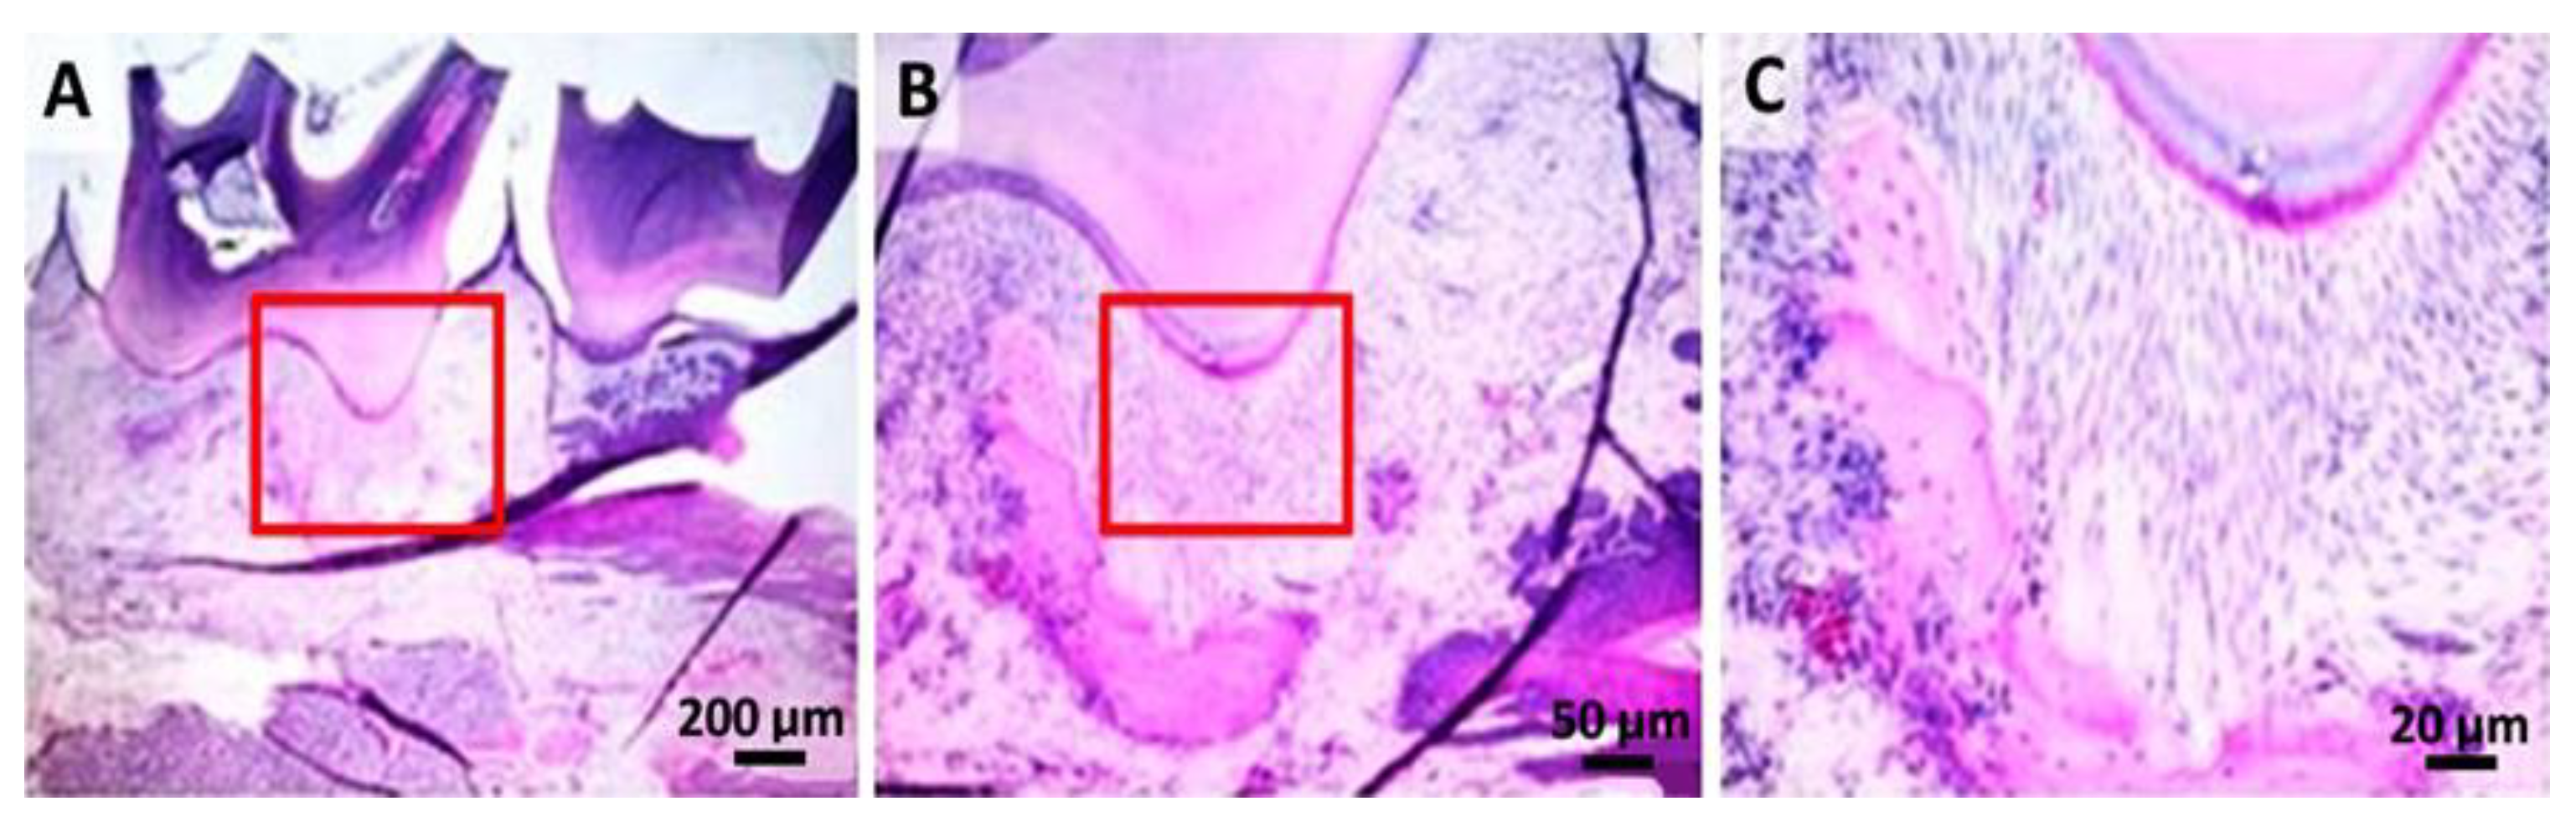

2.4. Histological Analysis

4.6. Histological Analysis